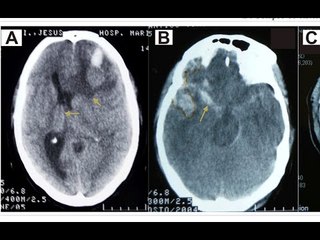

¿Cómo ayudar a una víctima de un infarto cerebral?